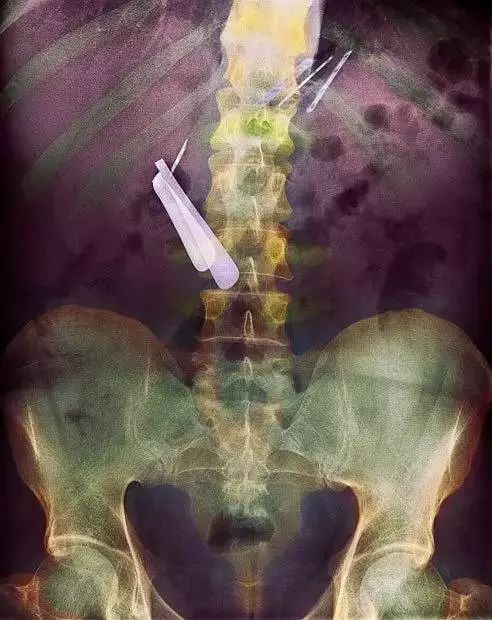

1、这是一名患有痴呆症的病人,通过对其腹部进行X光后,才发现她吞下了一根刮胡刀以及几片刀片!